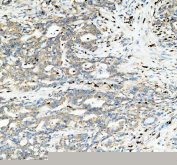

IHC testing of FFPE human lung cancer with mtTFA antibody. HIER: Boil the paraffin sections in pH 6, 10mM citrate buffer for 20 minutes and allow to cool prior to staining.